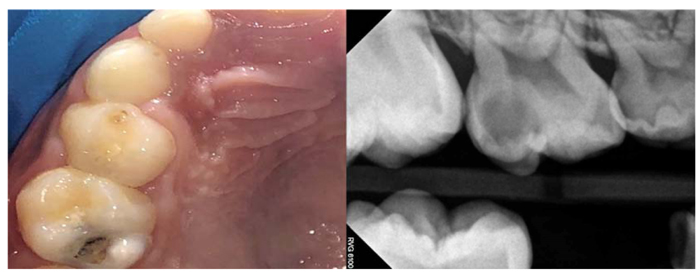

Dental caries have a continuum status. It starts in the very early stage with a subclinical non-cavitated lesion. It then becomes visible when it is converted into an early enamel lesion. After that, caries can develop into an established dentin lesion (Fig. 2), and it sometimes end up with a severe lesion reaching the pulp [7, 8]. It is critical to manage non-cavitated carious lesions as early as possible. However,these lesions have traditionally been detected at the cavitation stage, and their management has focused strongly on operative treatment [9].